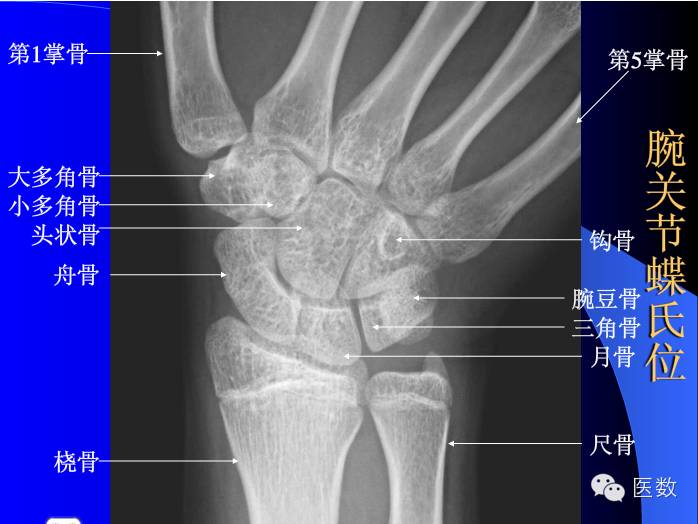

上肢骨关节解剖的x光投影

五分钟读图 正常骨骼不同体位x光片解读及常见骨折高精图谱

手腕x光图片

手掌x光图片